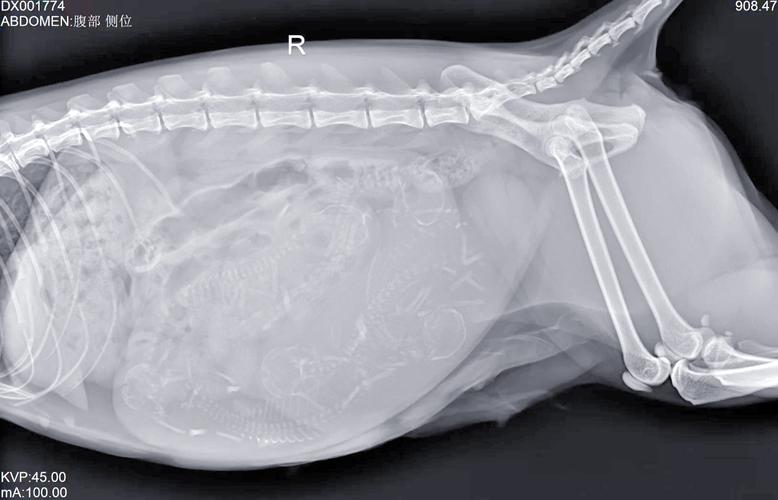

〖One〗、猫咪不能过安检的X光。安检的X光是可以照出猫咪的,且安检X光的辐射剂量可能对猫咪的健康造成潜在风险,因此不建议带猫咪通过安检X光。如果要携带猫咪出行,比较好是按照国家铁路的相关规定办理托运手续。具体流程包括:提前办理防疫证明:至少提前一个星期去附近的兽医站打狂犬疫苗和猫三联,取得防疫证。

〖Three〗、安检能够扫描出来猫。以下是对此问题的详细解安检设备能力:安检设备,如X光机,具有强大的扫描能力,能够检测出携带的物品和生物体,包括猫等宠物。因此,如果尝试携带猫通过安检,设备很可能会扫描并识别出来。